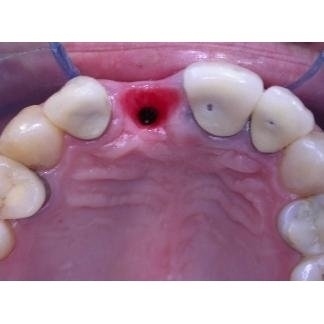

Visione occlusale dell'impianto in posizione sottogengivale.Dopo il periodo di osteointegrazione dell'impianto (circa 3 mesi), è stato posizionato un provvisorio avvitato.